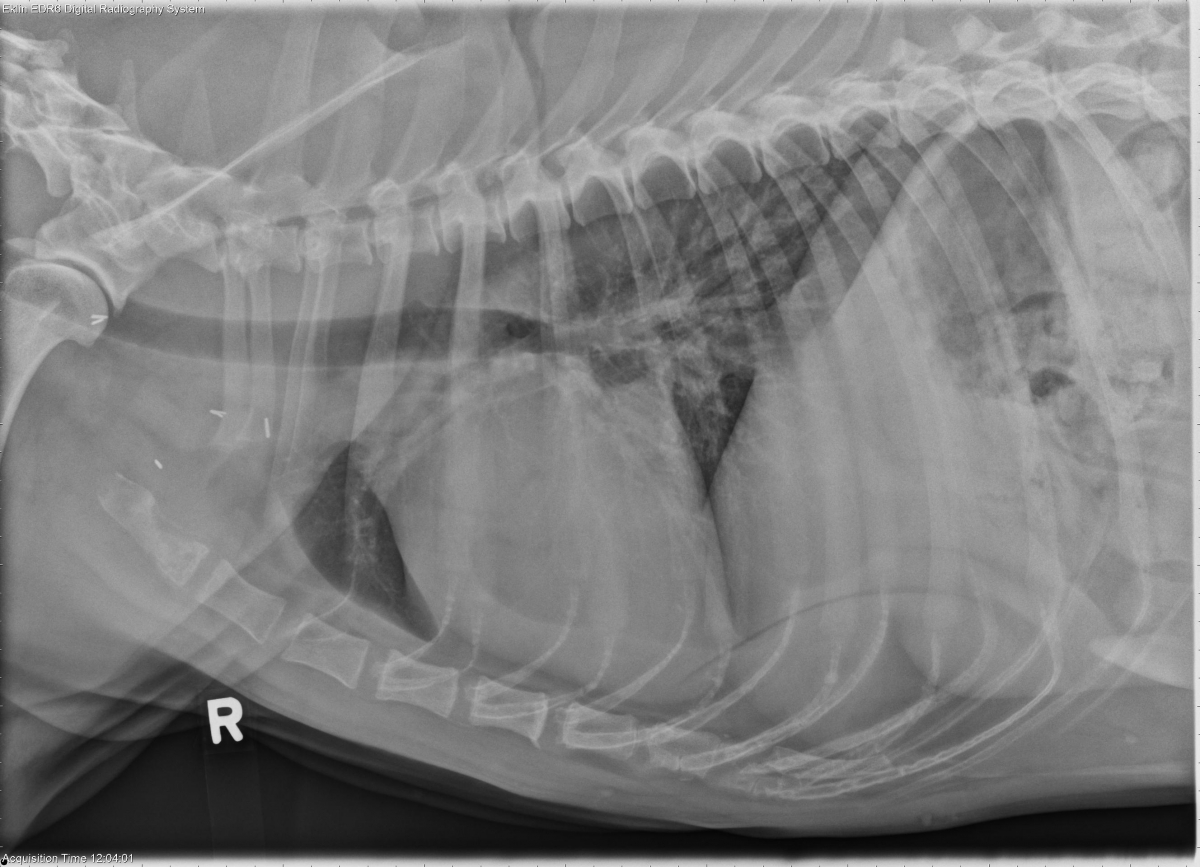

Today’s case is a 6 year old male Spaniel with previous amputation performed for left thoracic limb osteosarcoma. What are your findings?

The left thoracic limb is absent, and there are metallic staples in the soft tissues consistent with previous amputation. The cardiovascular structures are normal in size and shape. No abnormalities are seen in the pulmonary parenchyma, pleural space, or mediastinum. The first sternebra is radiolucent and irregular in appearance with subtle periosteal reaction. On the dorsoventral projection, there is expansion and lysis of the right 6th rib. These findings are confirmed on collimated projections. There is osteophyte production surrounding the right shoulder joint.

Osteosarcoma metastasis to the right 6th rib and first sternebra.